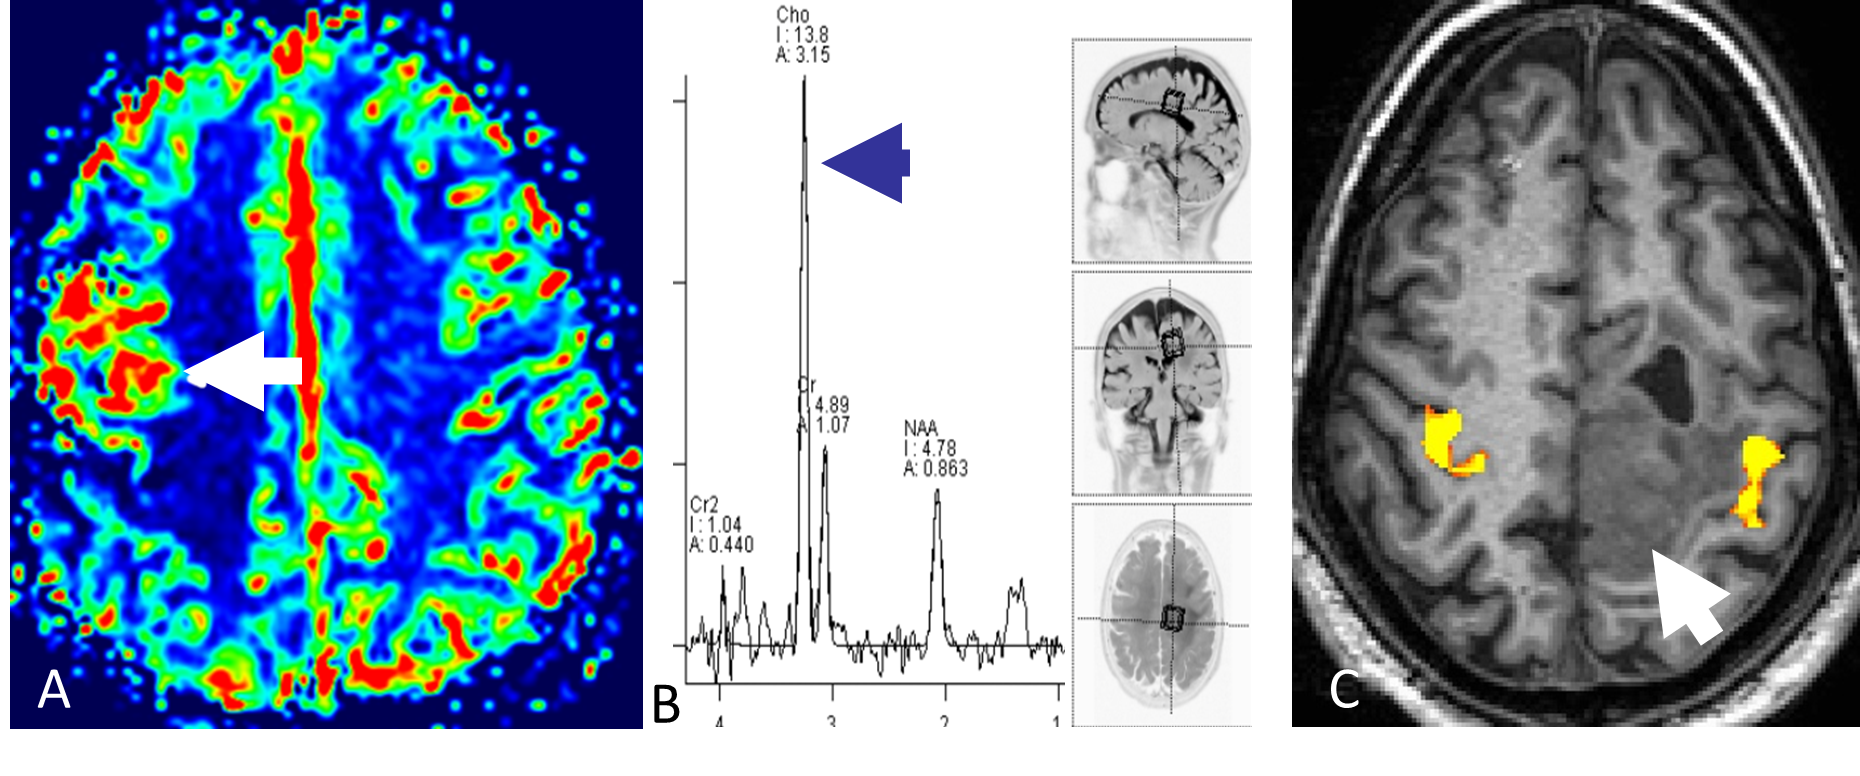

MR-perfusjon

Ved å gi en rask intravenøs injeksjon med kontrastmiddel og deretter følge kontrastens passasje gjennom kapillærsirkulasjonen i hjernen, kan man ved MR-perfusjon få informasjon om variabler som blodvolum og blodperfusjon i hjernevev og tumor. Høygradig maligne svulster har typisk mange og store tumorkar og har derfor høyere blodvolum og perfusjon enn lavgradige svulster (Figur 5.2). MR-perfusjon kan videre differensiere svulster fra andre tilstander, for eksempel vil strålenekrose oftest ha lavt blodvolum og lav blodperfusjon (Mabray et al., 2015).

MR-spektroskopi (MRS)

MRS gir informasjon om biokjemiske forhold i hjerneparenchymet. Hydrogenkjerner har litt ulike MR-egenskaper avhengig av hvilket molekyl de er bundet til. Ved MRS brukes disse små forskjellene til å lage et spekter hvor toppene representerer ulike metabolitter og størrelsen på toppene indikerer konsentrasjonen i vevet. Ved en rekke tilstander endres vevets biokjemi; i maligne svulster øker for eksempel mengden av metabolitten cholin (Figur 5.2) (Mabray et al., 2015). Diagnostisk benyttes metoden særlig til å differensiere mellom ulike hjernesvulster og for å skille mellom tumor og annen type patologi.

BOLD fMRI

BOLD fMRI er en MR-metode som benyttes til kartlegging av hjerneaktivitet. I klinisk sammenheng benyttes BOLD fMRI særlig til å kartlegge viktige kortikale områder før kirurgisk behandling av hjernesvulster (Figur 5.2). Metoden har dessuten fått svært stor betydning i nevrovitenskapen for å øke forståelsen av hjernens funksjoner.